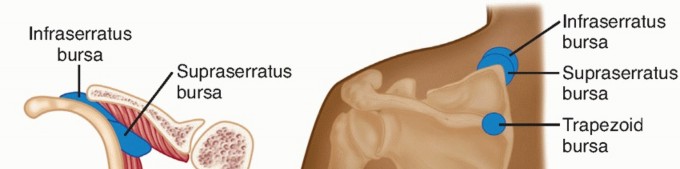

The scapulothoracic articulation consists of the interface between the anterior aspect of the scapula and the ribs in the posterior aspect of the convex thoracic chest wall (FIG 1).

The osseous anatomy of the scapula is variable.1 The scapulothoracic articulation is cushioned by several muscles, specifically the subscapularis and the serratus anterior. The serratus anterior has both a broad origin on the chest wall and a broad insertion along the majority of the ventral surface of the medial scapula (FIG 2).

FIG 1 • Four different bursae are shown—two infraserratus, one supraserratus, and one trapezoid bursae.

In addition, two major and four minor bursae have been described in the scapulothoracic articulation13,14,37 (see FIG 1*).

The two major bursae are the infraserratus bursa, located between the serratus anterior muscle and the chest wall, and the supraserratus bursa, located between the serratus anterior and the subscapularis muscles.

The four minor bursae are distributed as follows: two at the superomedial angle of the scapula, one at the inferior angle of the scapula, and one at the medial base of spine of the scapula, underlying the trapezius muscle.

Although the major bursae have been found consistently in cadaveric and clinical studies, those of the minor bursae were not.8,33,34

FIG 1 • Four different bursae are shown—two infraserratus, one supraserratus, and one trapezoid bursae.

In addition, two major and four minor bursae have been described in the scapulothoracic articulation13,14,37 (see FIG 1*).

The two major bursae are the infraserratus bursa, located between the serratus anterior muscle and the chest wall, and the supraserratus bursa, located between the serratus anterior and the subscapularis muscles.

The four minor bursae are distributed as follows: two at the superomedial angle of the scapula, one at the inferior angle of the scapula, and one at the medial base of spine of the scapula, underlying the trapezius muscle.

Although the major bursae have been found consistently in cadaveric and clinical studies, those of the minor bursae were not.8,33,34